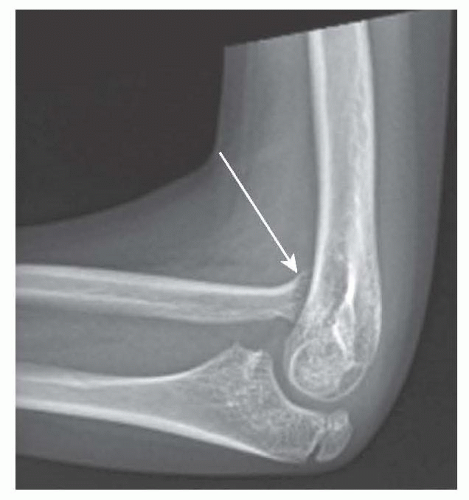

IMAGING

Anteroposterior and lateral radiographs of the elbow or wrist may be obtained to evaluate for joint subluxation/dislocation or articular deformities (FIG 1).